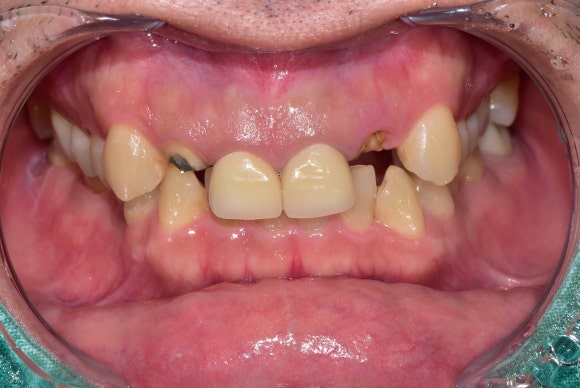

오늘은 30대 남성분의 이야기입니다.

사회활동이 가장 활발한 30대 남성에게,

어느 날 앞니 두 개가 사라져버렸습니다.

예전에 신경치료하고 크라운으로

씌워둔 치아인데,

어느 날 갑자기

약속이라도 한 듯이

양쪽 크라운이 뚝! 하고 부러졌다고 합니다.